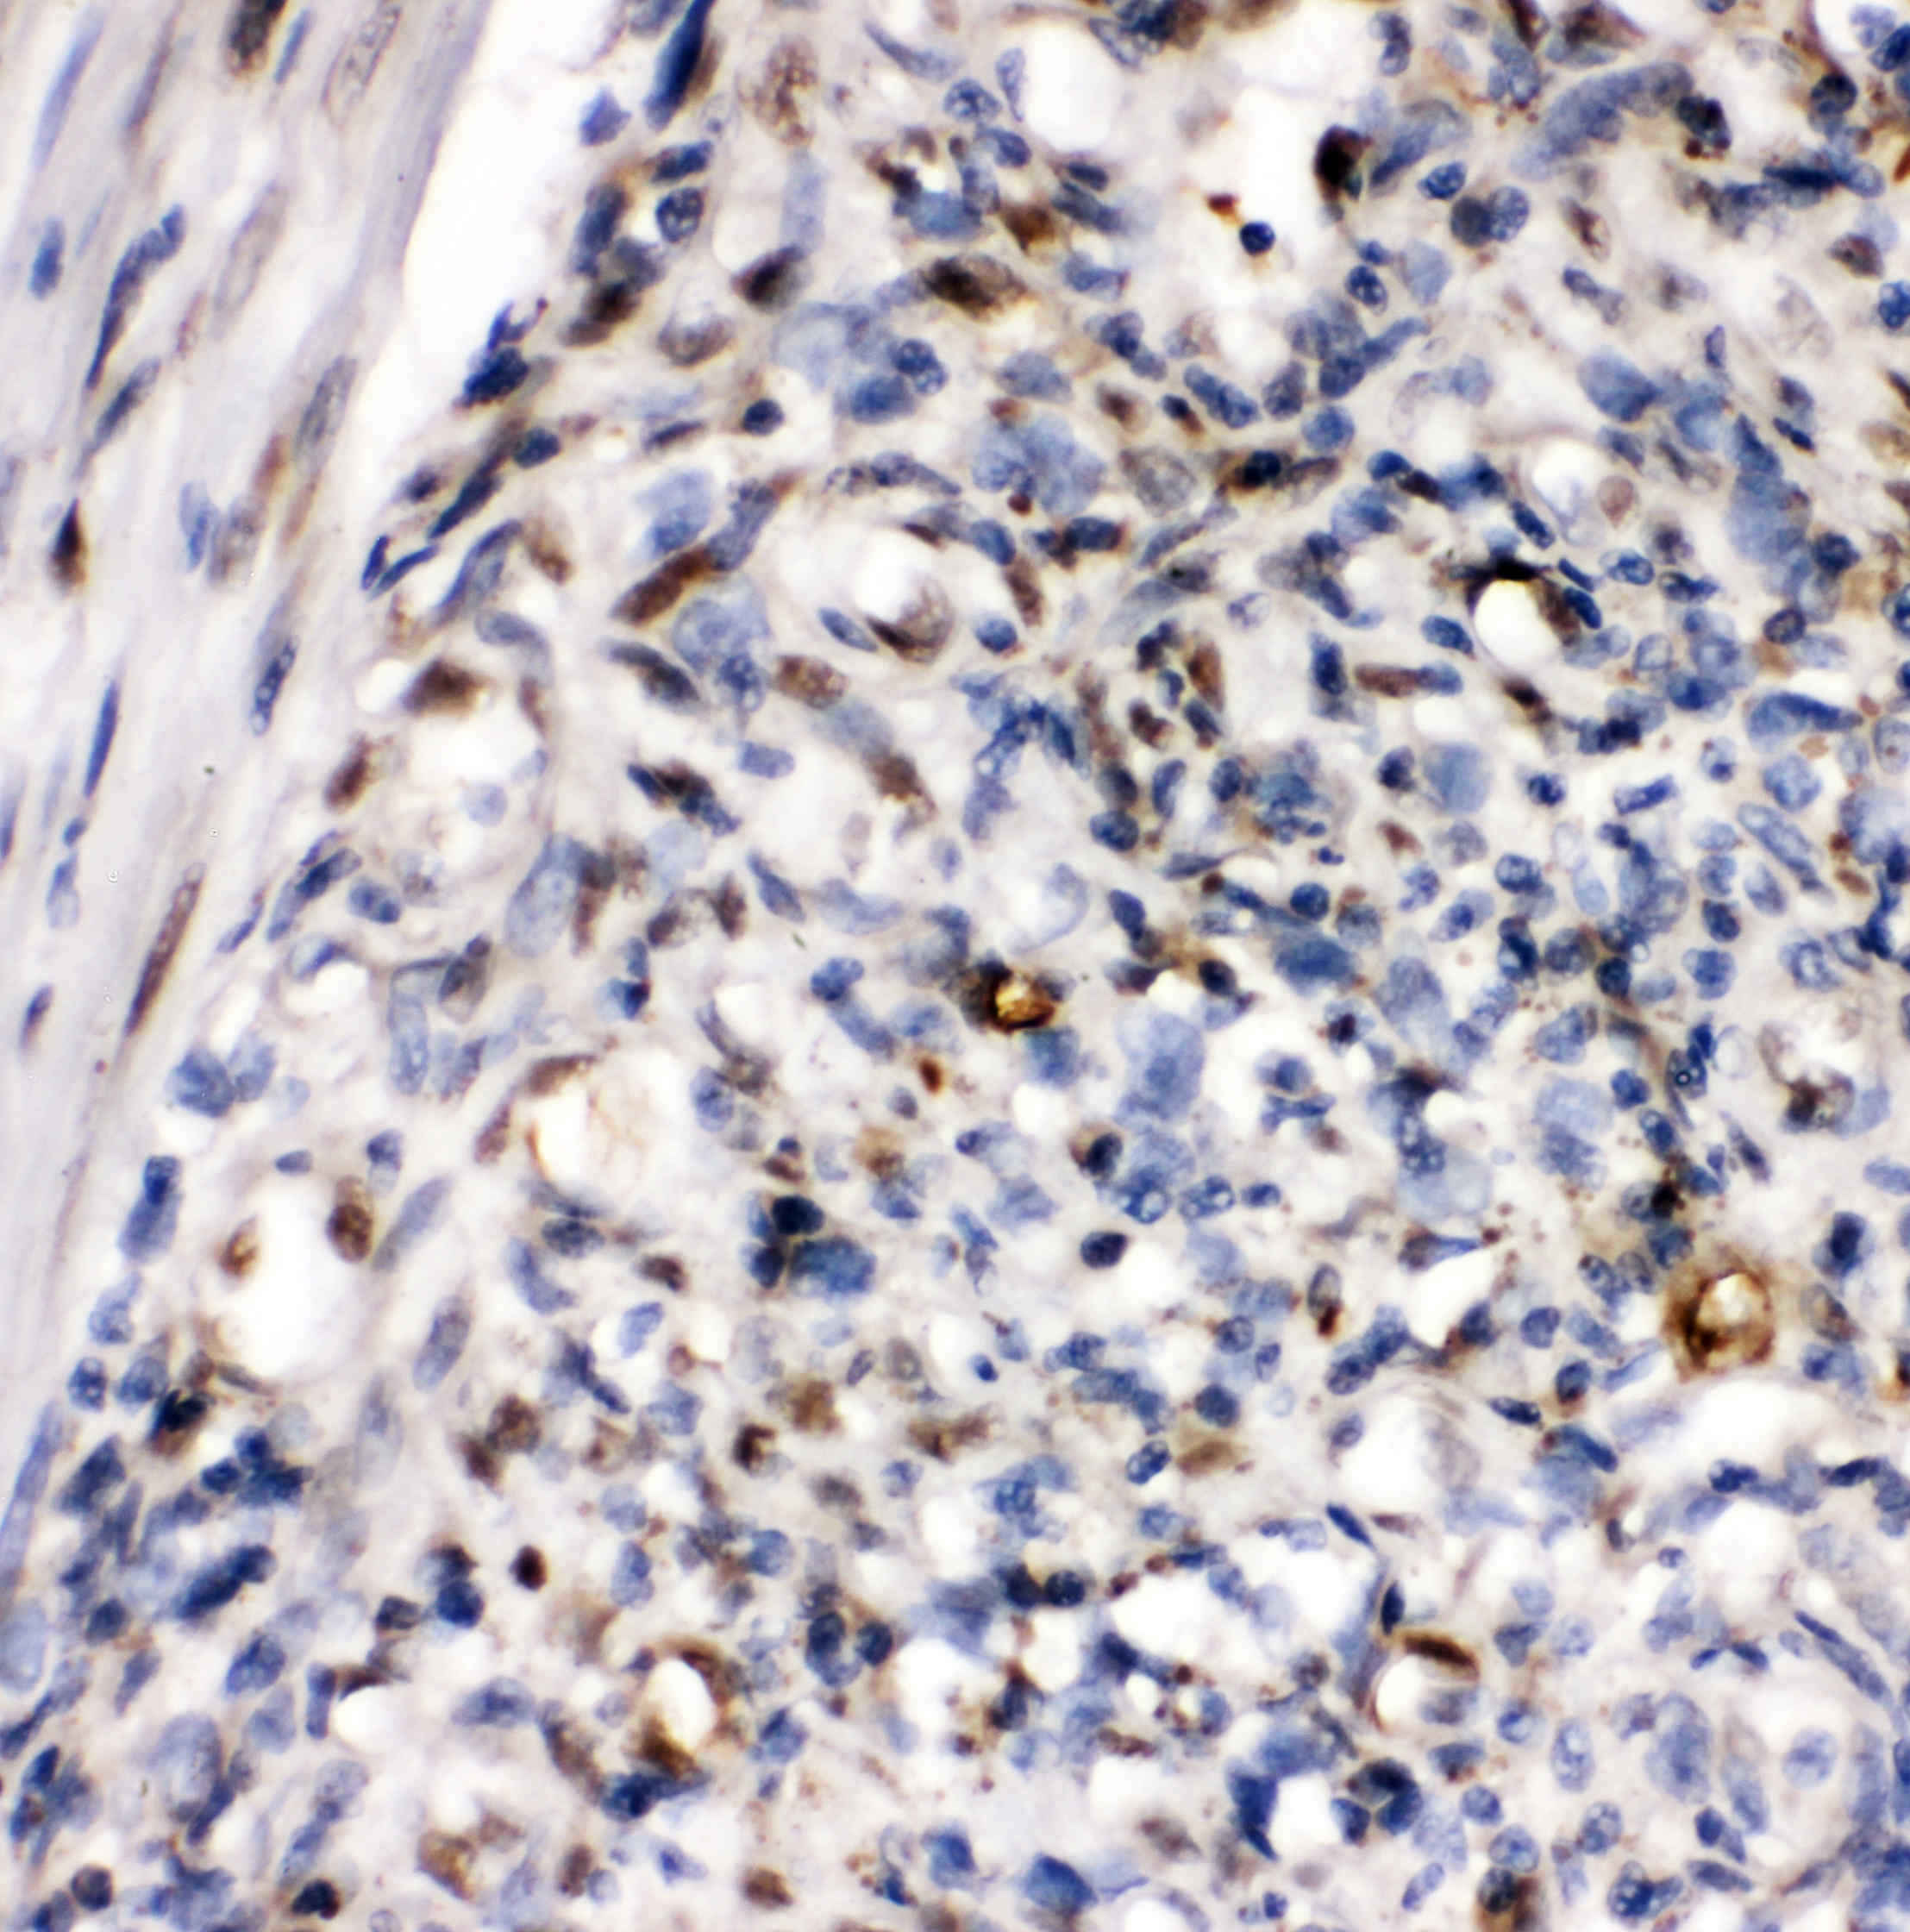

IHC analysis of ZEB1 using anti-ZEB1 antibody (A00548-2).

ZEB1 was detected in a paraffin-embedded section of human melanoma tissue. Biotinylated goat anti-rabbit IgG was used as secondary antibody. The tissue section was incubated with rabbit anti-ZEB1 Antibody (A00548-2) at a dilution of 1:200 and developed using Strepavidin-Biotin-Complex (SABC) (Catalog # SA1022) with DAB (Catalog # AR1027) as the chromogen.